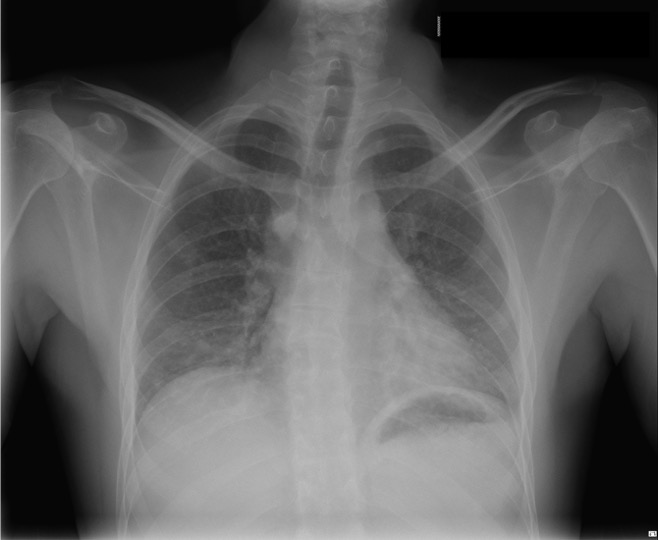

CASO: Dolor súbito en paciente asmático.

- Por la clínica presentada, debemos descartar un posible neumotórax. Sin embargo estamos ante una placa radiográfica con mala técnica.

- Se recomendó volver a realizar la radiografía, observar a continuación:

EXPOSICIÓN:

La penetración es la correcta cuando podemos visualizar la vértebras en su totalidad y las costillas a través del corazón.

El contraste es el adecuado si se pueden difrenciar adecuadamente estructuras con diferentes densidades: partes blandas, plumón y esqueleto.

La definición es buena si conseguimos que el paciente esté totlamente quieto durante la realización de la placa.